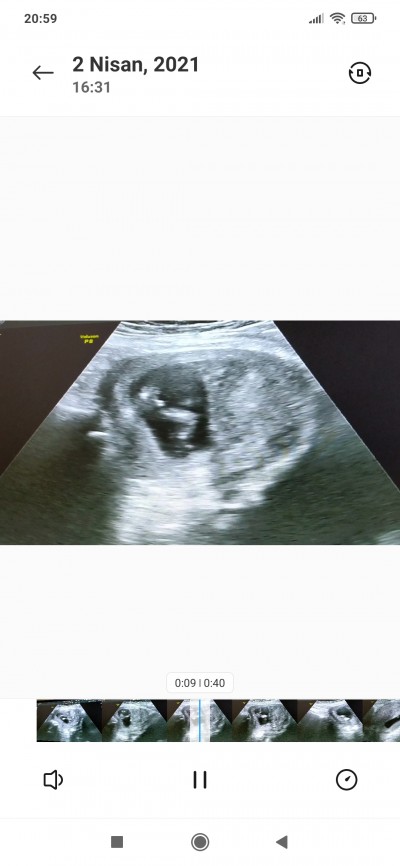

Slm kizlar ya bebisimin videosunda bı kaç ekran görüntüsü aldım bacak arasında bişey var ama pipimi kordonmu başka biseymi çözemiyorum anlayan yada başından geçen varsa bilen varsa yorum yaparsa sevinirim  ☺️

resimde dikkatli bak canım iki bacak ve arası görünüyor doktor erken diye bişey diyemedi sonra kıza yakın falan dedi emin olamadi bı daki kontrolde soyluycekmis merak ettim tabi duramadim ☺️

Kız o kadar pipi olmaz o kordon da. Sanki taş taşları gördüm gibi geldi =)

Gönül istiyorki iki duygudanda tadalim kızlarım benim için çok kıymetli yerleri başka ama oğlumda olsun o duyguyu da tadayim istiyorum tabi doktor kıza yakın falan dedi ama 11.haftada yüzde 60 erkek demişti 13.haftada kıza yakın dedi kafam karıştı nub teorisine göre erkek ve dogrulu yüzde 98 mis inşallah çıkar hayırlısıyla☺️☺️☺️

Benim ultrason da da böyle bişey var bende kordon sandim doktor erkek dedi iyice emin olayim diye bekledim en son testisleri falan oluşmuştu gittiğim de erkek hayırlısı olsun. Canım

Kordona pek benzemiyo pipi bence

Nasıl anlatsam bilemedim :D ayakları havada duruyor ortada 3 tane yuvarlak gözüken pipisi. Yani bize poposu dönük ayaklar yukarıda :D

Doktor hiç yorum yapmadı mi canm bu kadar net gozuken pipi olsa doktor söylerdi senin gördüğünü eminim oda görürdü ben 11+4de öğrendim erkek demişlerdi

11 haftada erkeğe benzetti 13 haftada kıza yakın dedi ama pozisyonu falan iyi değildi göremedi bide çok hareket ediyordu canim